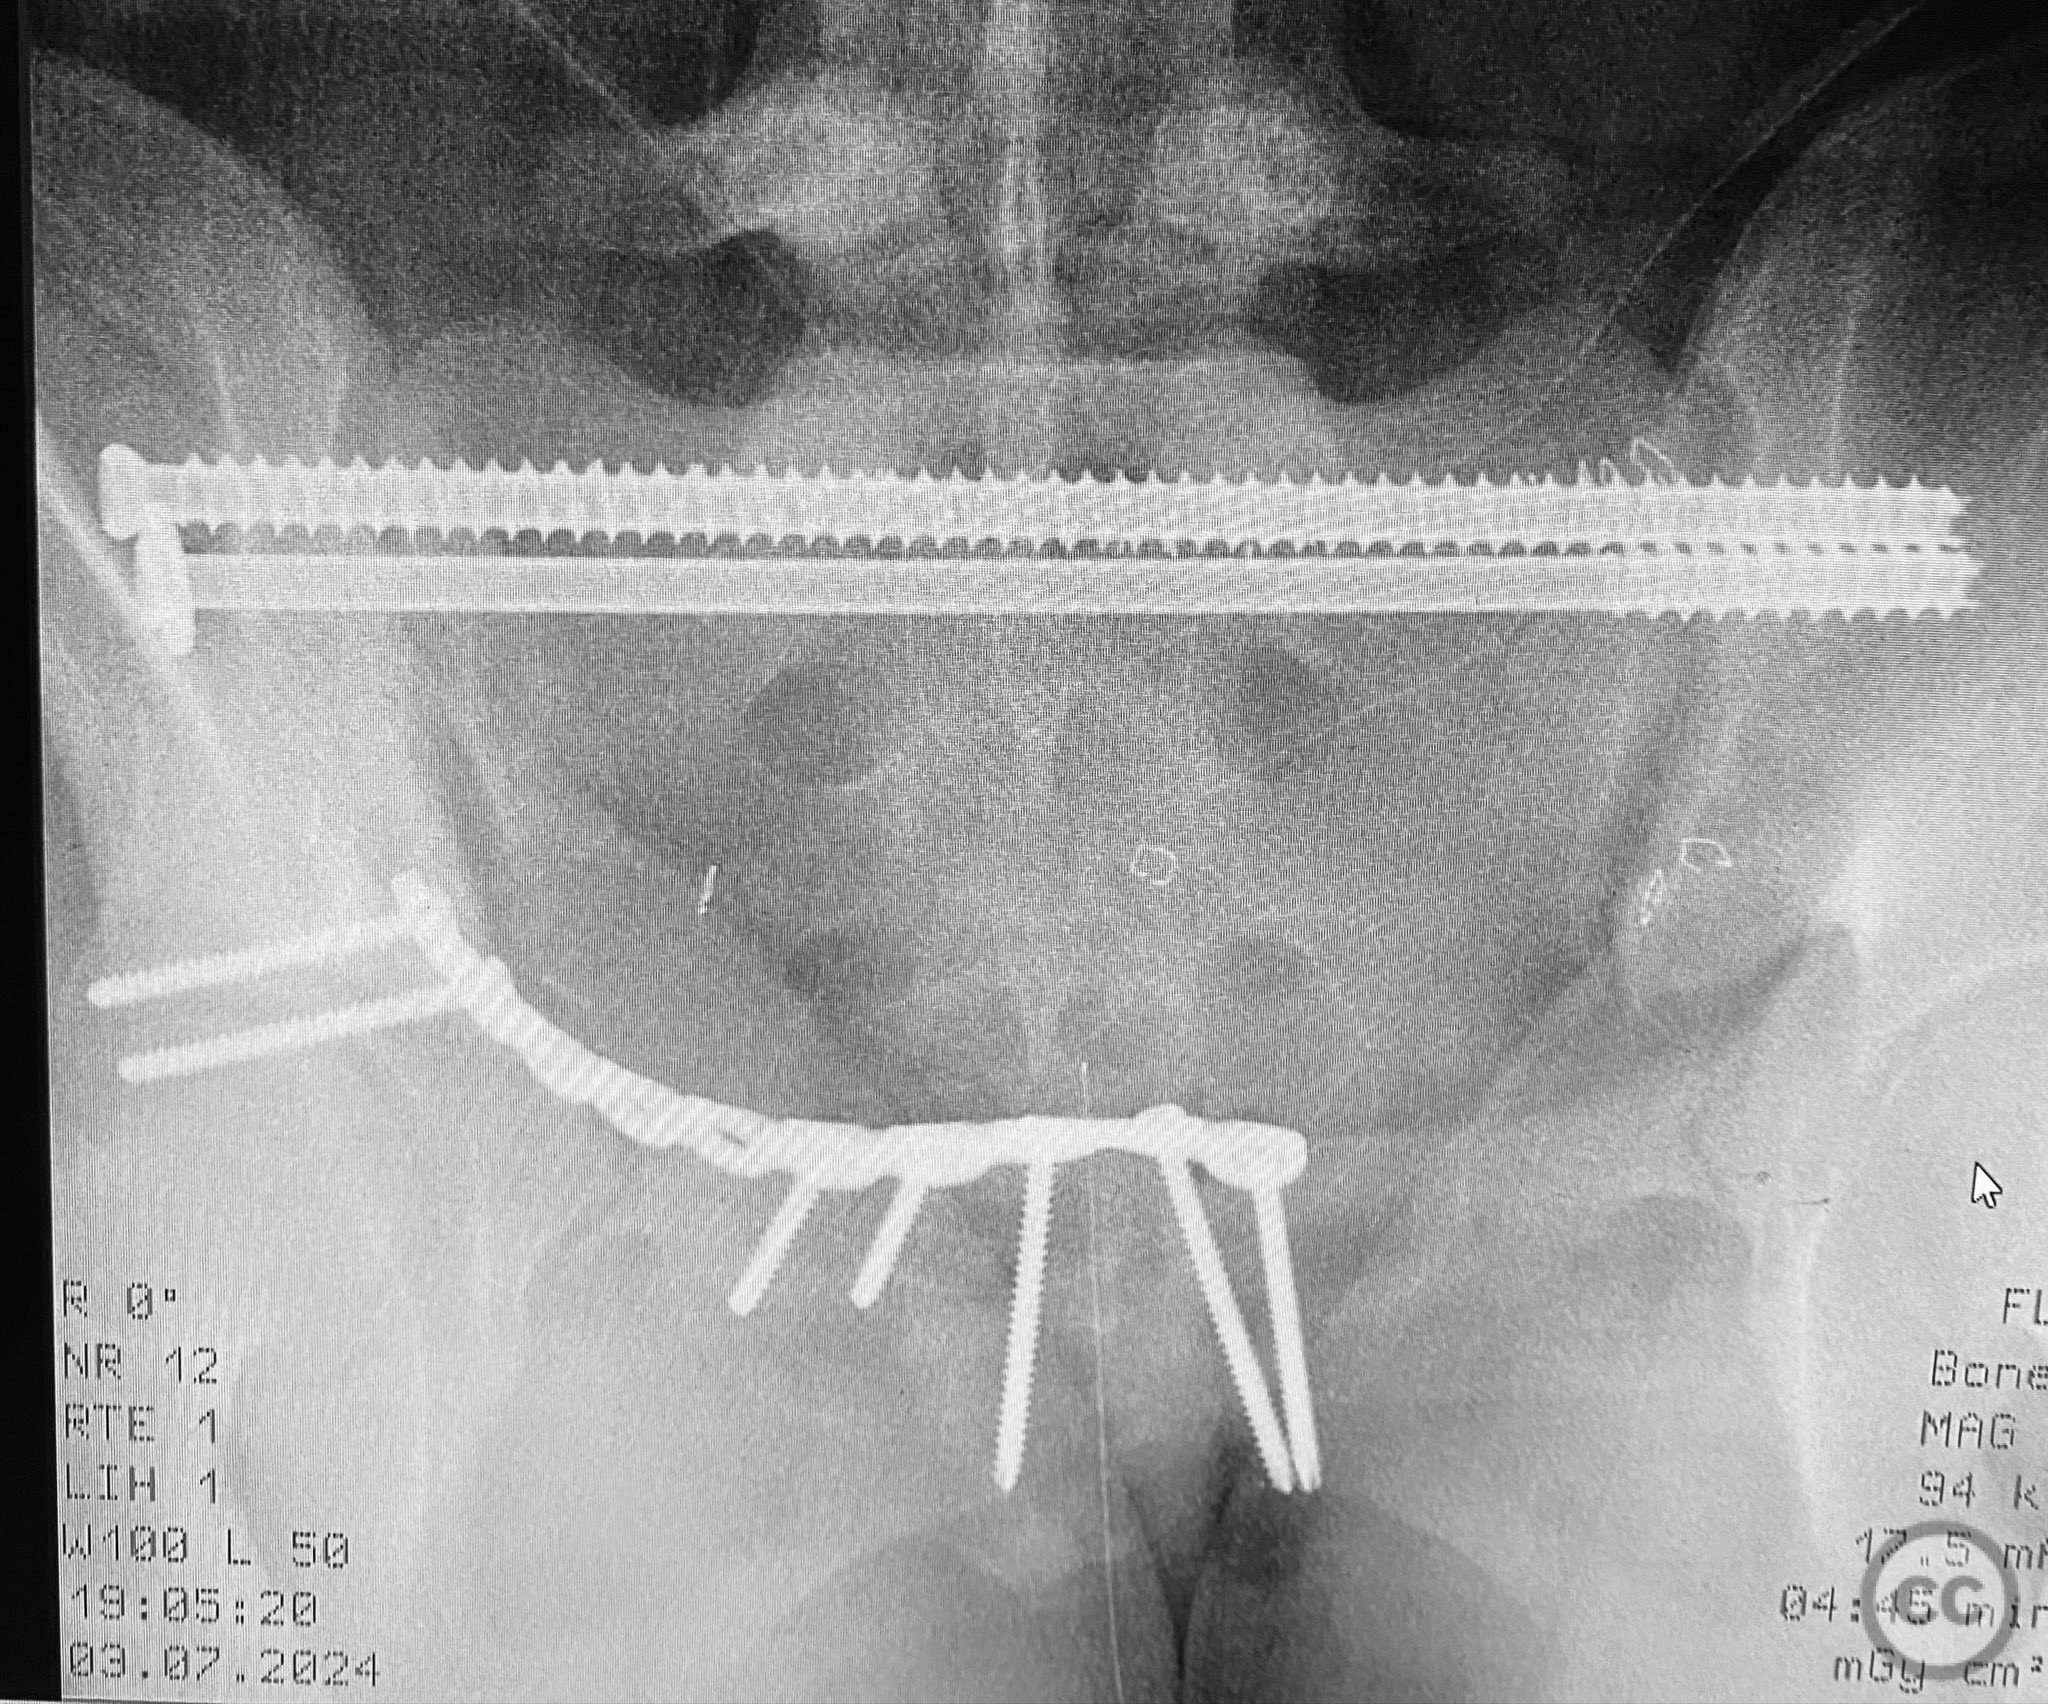

Anatomical surgical approach:  A combined Pfannenstiel and intrapelvic (modified Stoppa) approach was utilized. A transverse suprapubic skin incision was made approximately two fingerbreadths above the symphysis pubis. Dissection proceeded through the subcutaneous tissue and rectus sheath, with careful subperiosteal elevation of the rectus abdominis from the anterior pelvic ring. The retropubic space (Cave of Retzius) was developed to expose the symphysis pubis and superior pubic rami bilaterally. Intrapelvic exposure allowed direct visualization and reduction of the displaced right pubic ramus fracture and symphyseal diastasis. A pre-contoured plate was applied to the anterior ring using both direct and indirect reduction techniques.

Operative remarks:

Intraoperative fluoroscopy with AP and inlet views, as well as dynamic positioning of the lower extremities, was critical in fully delineating the extent of injury, which had been underestimated on preoperative imaging due to binder application. The excessively curved morphology of the right pubic ramus precluded safe or effective straight screw fixation; therefore, ORIF with a contoured plate was performed using intrapelvic exposure for optimal fit and stability. Indirect closed reduction of the SI joints was accepted, followed by percutaneous trans-sacral screw fixation under fluoroscopic guidance. This case highlights the necessity of thorough intraoperative assessment for occult or underestimated injury patterns in complex pelvic trauma, particularly when initial imaging is performed with a pelvic binder in situ.

Orthopaedic implants used:   Pre-contoured anterior pelvic reconstruction plate; percutaneous trans-sacral cannulated screws